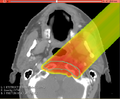

File:Project25 EBP a.png

Project25_EBP_a.png (645 × 530 pixels, file size: 79 KB, MIME type: image/png)